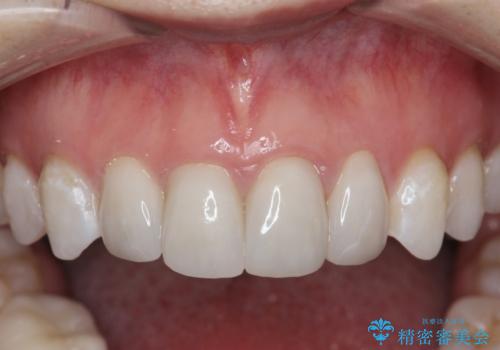

仮歯のまま放置していた前歯をセラミックに

- 52.8万円(ジルコニアクラウン×4・仮歯×4)費用は治療当時の料金となります

セラミッククラウンは長期的に変色しづらく、汚れのつきにくい審美製を長期的に保つことのできる治療方法です。